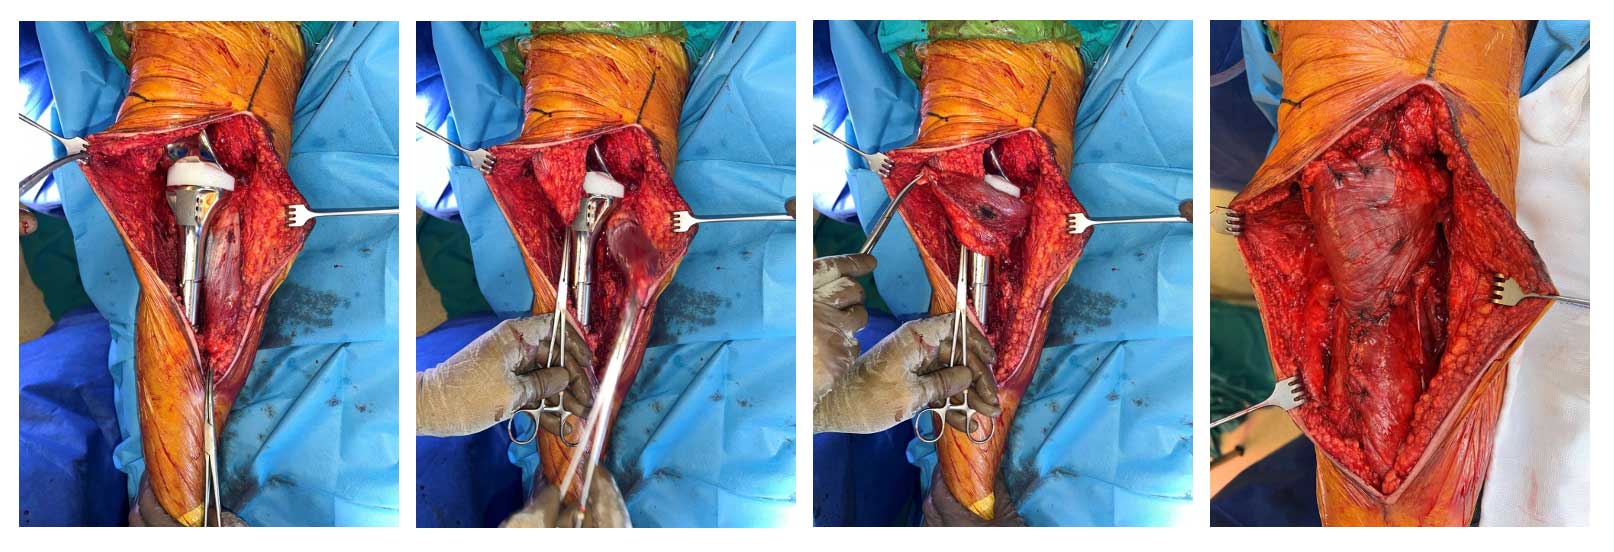

Hastaya kemoterapi sonrasında geniş rezeksiyon uygulandı. Tümörlü kemik çıkarıldıktan sonra diz eklemi ve çevre dokuların bütünlüğü korunacak şekilde tümör protezi ile yeniden yapılandırma (rekonstrüksiyon) yapıldı. Yumuşak doku kapatılması için gastroknemius kas flebi kullanılarak sağlam ve estetik bir doku örtüsü elde edildi.

Ameliyat Esnası: Çıkarılan tümör dokusunun klinik ve skopi görüntüsü.

Ameliyat Esnası: Tümör protezi, patellar tendon, gastroknemius flep ve kapama.